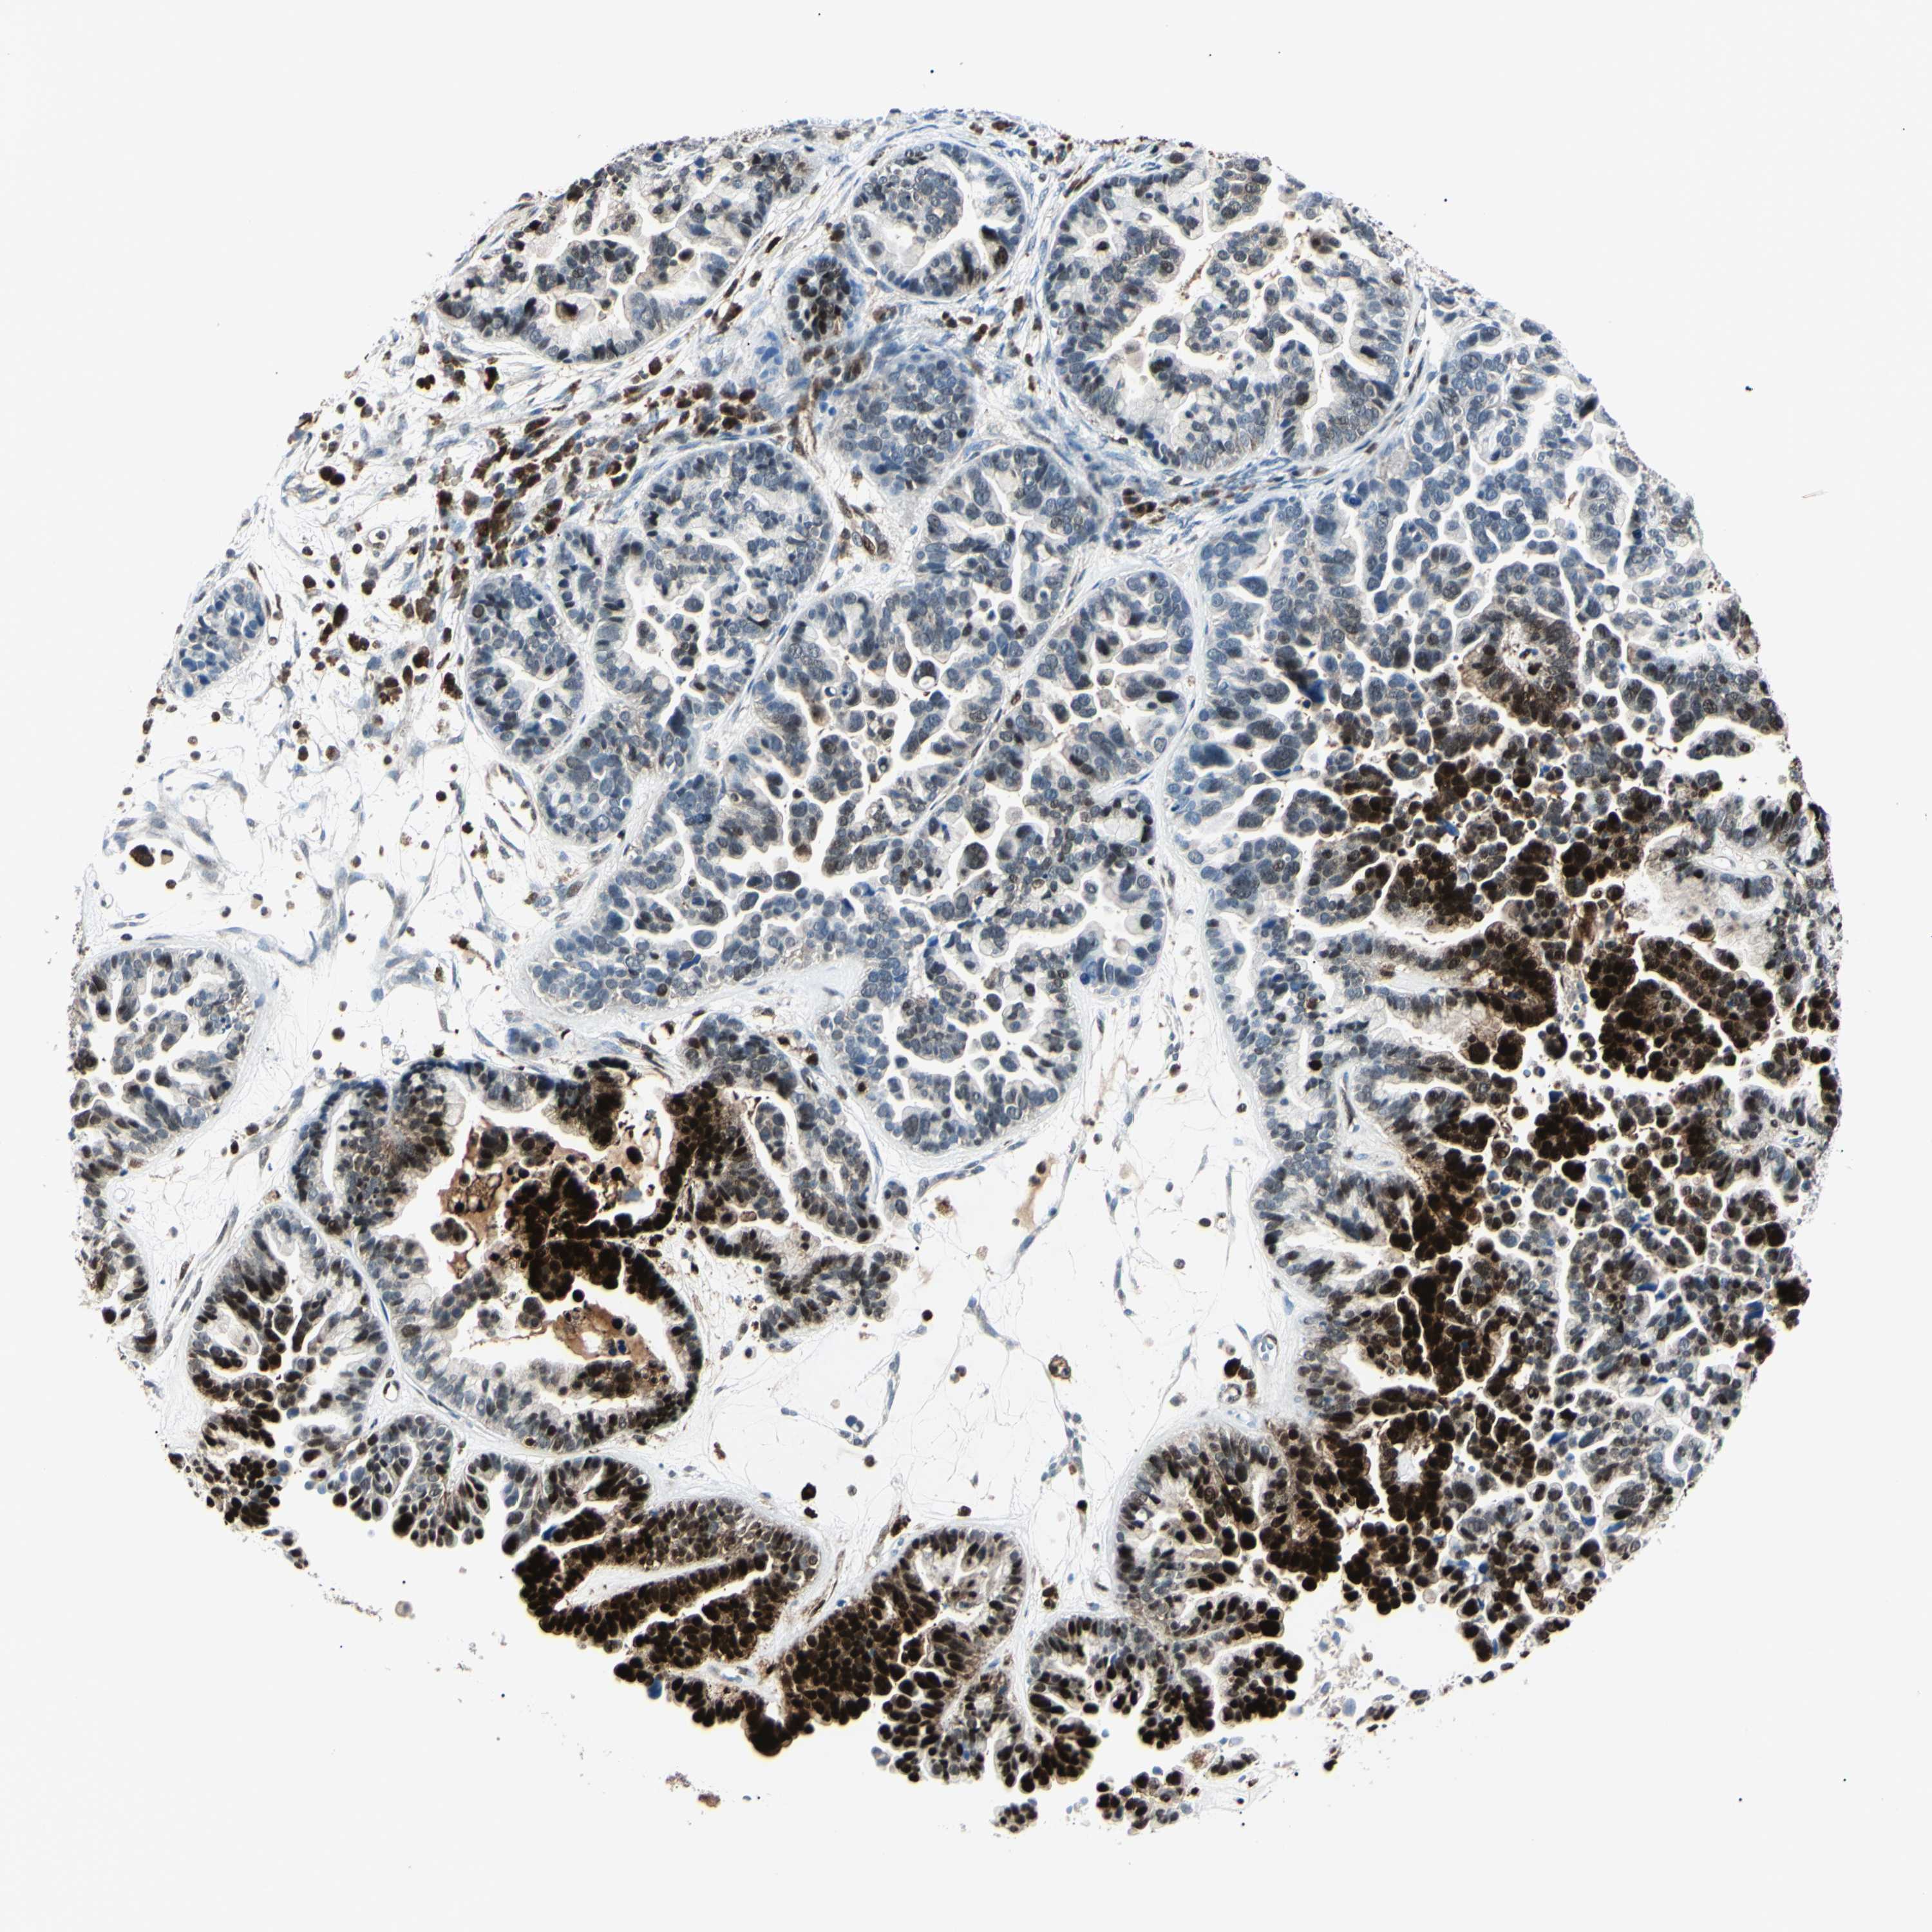

OVARIAN CANCER - Protein expressioni

A mouse-over function shows sample information and annotation data. Click on an image to view it in a full screen mode. Samples can be filtered based on level of antibody staining by selecting one or several of the following categories: high, medium, low and not detected. The assay and annotation is described here.

Note that samples used for immunohistochemistry by the Human Protein Atlas do not correspond to samples in the TCGA dataset.

Antibody stainingi

Antibody staining in the annotated cell types in the current human tissue is reported as not detected, low, medium, or high, based on conventional immunohistochemistry profiling in selected tissues. This score is based on the combination of the staining intensity and fraction of stained cells.

Each image is clickable and will lead to virtual microscopy that enables deeper exploration of all samples and also displays staining intensity scores, fraction scores and subcellular localization as well as patient and tissue information for each sample.

Antibody HPA045385

Antibody HPA073644

Antibody HPA073656

Antibody CAB010065

Staining

High

Medium

Low

Not detected

Intensity

Strong

Moderate

Weak

Negative

Quantity

>75%

75%-25%

<25%

None

Location

Nuclear

Cytoplasmic/membranous

Cytoplasmic/membranous,nuclear

Cystadenocarcinoma, serous, NOS

Carcinoma, NOS

Cystadenocarcinoma, mucinous, NOS

Carcinoma, endometroid